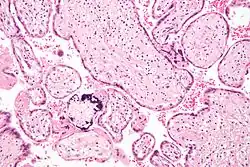

Micrograph of CMV placentitis -